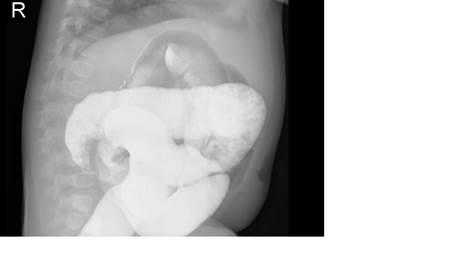

На рисунках 4 и 5 представлена картина кишечной инвагинации при рентгенологическом исследовании.

Рис. 4. Ирригограмма при тугом наполнении взвесью сульфата бария - симптом «клешней рака»

Комментарий: для дополнительной диагностики инвагинации кишечника допустимо использование рентгенографии (рентгеноскопии). При инвагинации кишечника на обзорных рентгенограммах органов брюшной полости, выполненных в вертикальном положении может отмечаться малое газонаполнение правого нижнего квадранта живота и признаки кишечной непроходимоти - расширенные петли кишечника с уровнями жидкости. В случае перфорации стенки ущемленной кишки и развитии перитонита - определяется свободный газ в брюшной полости (серповидная полоска просветления над печенью). Однако подобная рентгенологическая картина неспецифична для инвагинации кишечника. Более полные сведения при подозрение на инвагинацию кишечника дает контрастная ирригография. В качестве контраста в случае подозрения на инвагинацию кишечника целесообразно использование воздуха (пневмоирригография). При выполнении пневмоирригографии ребенка укладывают на стол рентгенологического аппарата в горизонтальном положении. Нагнетание воздуха в ампулу прямой кишки производят баллоном Ричардсона через катетер. Воздух в кишку нагнетают медленно и осторожно. По мере заполнения воздухом толстой кишки головка инвагината определяется в виде гомогенной тени с четкими контурами. Расположение тени зависит от анатомического типа внедрения. Равномерное заполнение толстой кишки воздухом и проникновение его в начальный отдел подвздошной кишки позволяет исключить наличие инвагината в этом отделе кишечника, но не снимает диагноза тонкокишечного внедрения.